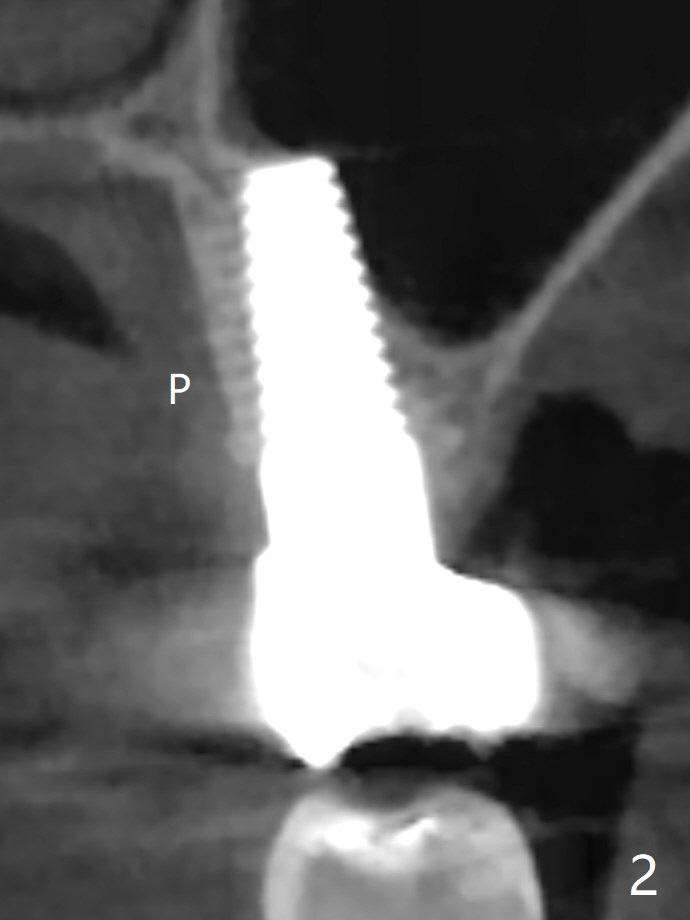

57岁女缺失2号牙多年,八年前14号牙折裂,根管治疗失败,改为即种(徒手),上颌骨骨质高度不足(图一),植体就一定植入上颌窦?近来15号牙又怀疑折裂,不愿接受根管治疗,要求种植。其实14号牙植体植入腭侧牙槽窝,顶端还有骨质,根尖颊侧多个螺纹似乎没有骨质覆盖,但是没有症状。15号牙上端上颌窦膜薄(图三),如果提升时窦膜完整,植入5x8.5毫米植体(图四),否则放置PRF,胶原塞,可以不植骨,植入5x7.3毫米植体(图五)。